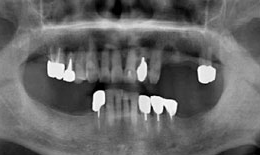

インプラント症例(21)75歳 男性

治療前

上顎

インプラントを2本埋め込んで、セラミックスクラウンを被せた

下顎

インプラントを4本埋め込んで、セラミックスクラウンを被せた